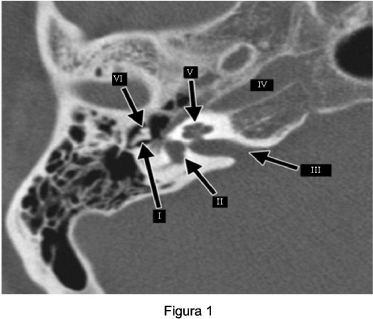

Observe a Figura 2 para responder a questão.

Com relação às estruturas anatômicas apontadas na Figura 2 é correto afirmar.

Com relação à Figura 2 é correto afirmar: